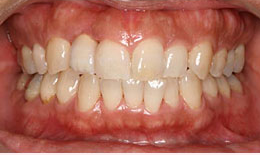

治療後

保存困難な歯を抜歯後、インプラントを1本埋め込み、セラミックスクラウンを被せた

治療の流れ

1. 最初に右上の歯を抜きます。

2. 歯茎が熟成するのを待って、インプラントを入れていきます。

3. 歯を入れて、歯茎の高さを調整して完成です。